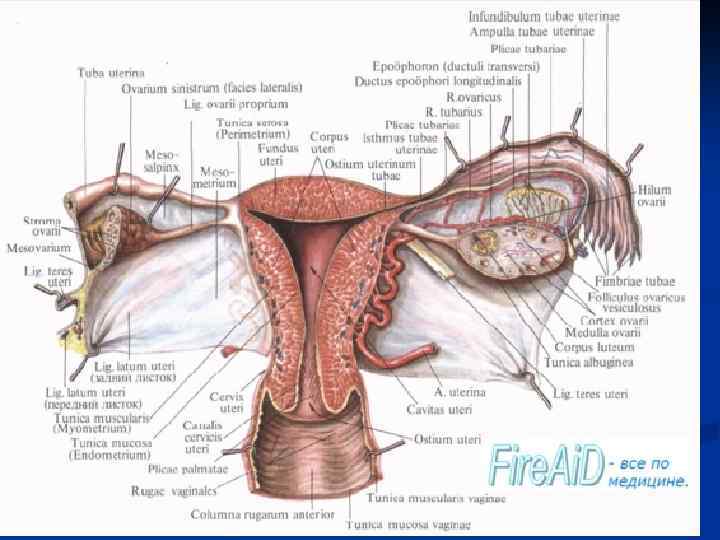

Женские половые органы, organa genitalia feminina

Женские половые органы, organa genitalia feminina